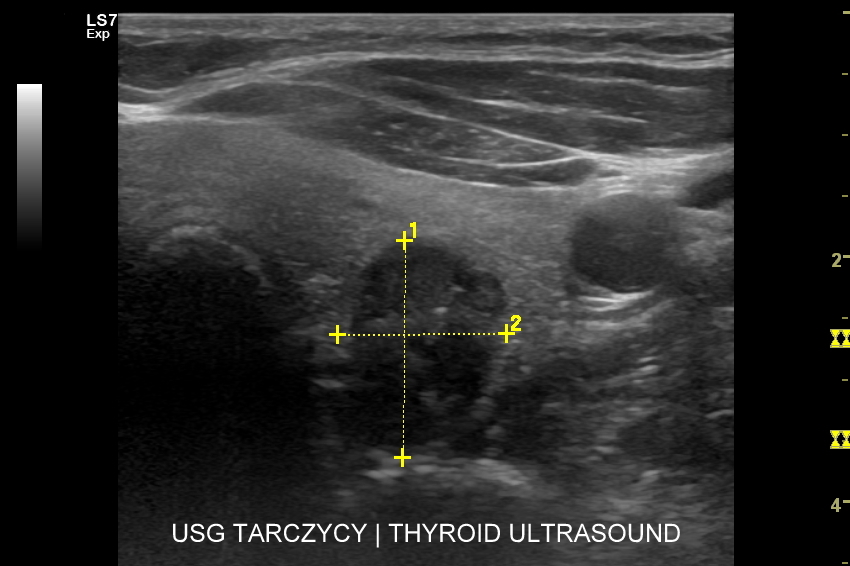

Czym jest guzek tarczycy? Guzek tarczycy jest określeniem dotyczącym uwypuklenia w zakresie szyi, które wywodzi się z gruczołu tarczowego. W potocznym języku jednakże pojęcie to odnosi się do tzw. zmian ogniskowych w tarczycy, tj. takich zmian, których wymiar można określić w trzech płaszczyznach. W obrębie zmian ogniskowych wyróżnia się torbiele oraz zmiany lite, w domyśle tkankowe.

Czy USG pozwala wykryć raka tarczycy? W sytuacji, gdy podczas badania USG stwierdzona zostanie zmiana ogniskowa w tarczycy, to dokonuje się jej oceny i gradacji w skali TIRADS. Skala ta określa prawdopodobieństwo zaistnienia raka tarczycy, a przez to wskazanie do przeprowadzenia biopsji.

Kiedy wykonać biopsję guzka tarczycy? Wskazania do wykonania diagnostycznej, aspiracyjnej biopsji  cienkoigłowej guzka tarczycy określa się na podstawie skali TIRADS (ang.  thyroid image reporting and data system). Istnieją skale TIRADS amerykańska, europejska oraz polska modyfikacja skali europejskiej (EU-TIRADS-PL). W każdej z wymienionych oceniane są różnorodne cechy zmiany ogniskowej tarczycy takie jak rozmiary, echogeniczność, struktura wewnętrzna, kształt, orientacja, obecność mikrozwapnień, zarysy, cechy naciekania. W skali TIRADS wyróżnia się 5 kategorii, a im wyższa kategoria tym wyższe ryzyko obecności raka. Biopsję guzka tarczycy przeprowadza się począwszy od kategorii 3, przy czym pod uwagę bierze się również wielkość guzka.